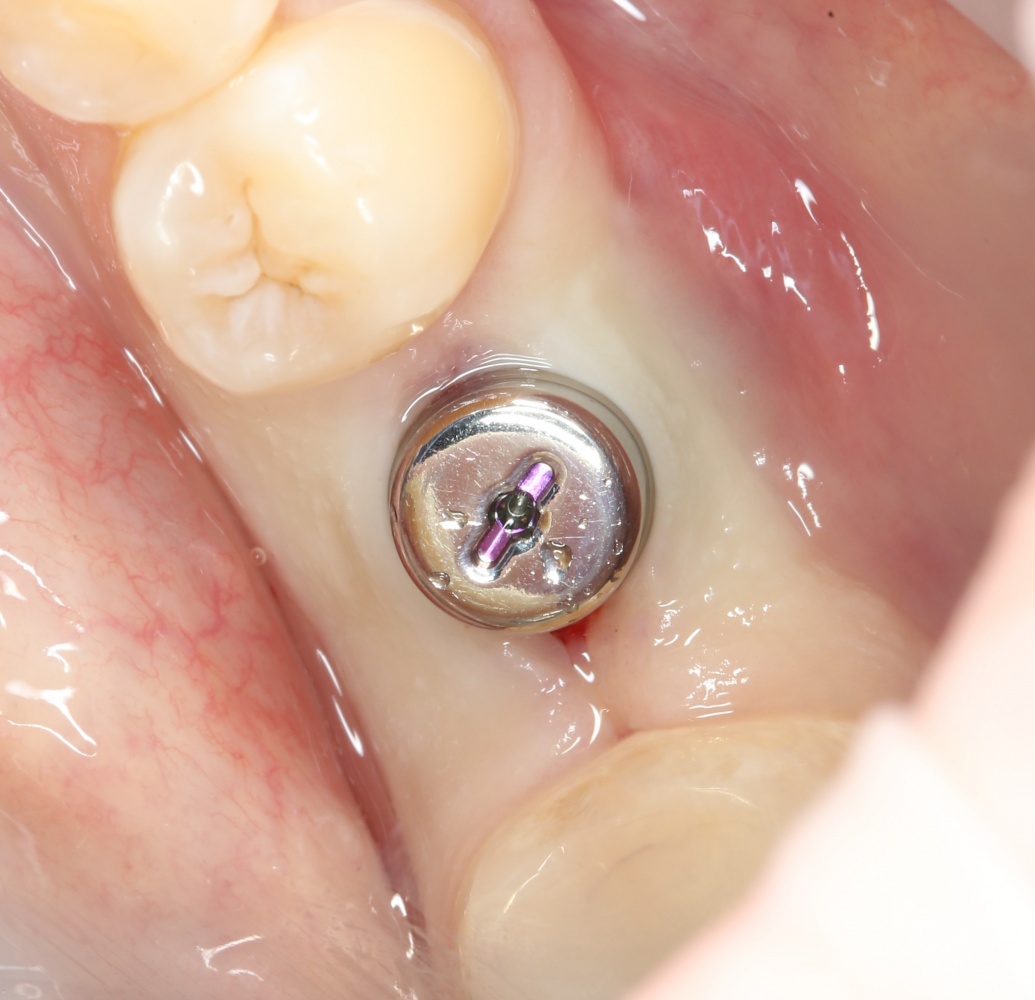

Рекомендации по установке имплантов. Для всех. Часть II.